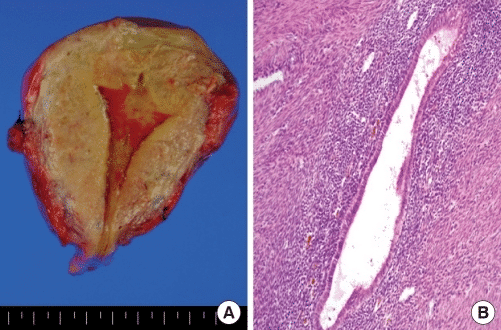

The invasion of endometrium can be focal or diffuse and is more commonly found in the posterior wall of the uterus. The extent of invasion is variable, but in severe cases pockets of menstrual blood can be seen in the myometrium of hysterectomy specimens.

When a collection of endometrial glands form grossly visible nodules, they are described as an adenomyoma. Oestrogen, progesterone and androgen receptors are found in the ectopic endometrial tissue, making it responsive to hormones.

Fig 1 - Pathological findings of hysterectomized uterus. (A) Gross appearance of adenomyosis. Note coarsely trabeculated, diffusely hypertrophied myometrium stippled with foci of ectopic endometrium. (B) Hematoxylin and eosin-stained section of uterus, showing endometrial glands and stroma surrounded by hypertrophied myometrium. Occasional hemosiderin-laden macrophages were also observed. Magnification, ×100.

Pathological findings of hysterectomized uterus. (A) Gross appearance of adenomyosis. Note coarsely trabeculated, diffusely hypertrophied myometrium stippled with foci of ectopic endometrium. (B) Hematoxylin and eosin-stained section of uterus, showing endometrial glands and stroma surrounded by hypertrophied myometrium.